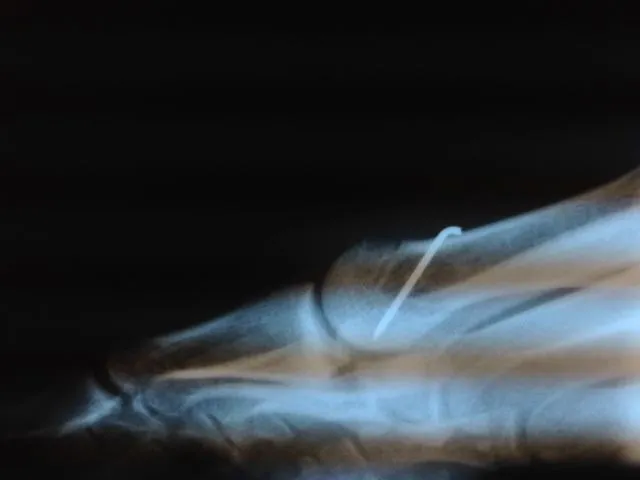

During surgical correction of the bunion a v-shape bone is made in most cases to translate the head of the 1st metatarsal laterally which creates an overhang of bone from the previous position of the bone (pictured left). The overhang is remove and the new position of the bone is held with some type of fixation which varies from screws, staples, or pins which is the case here. The pin is buried left in permanently (pictured right).